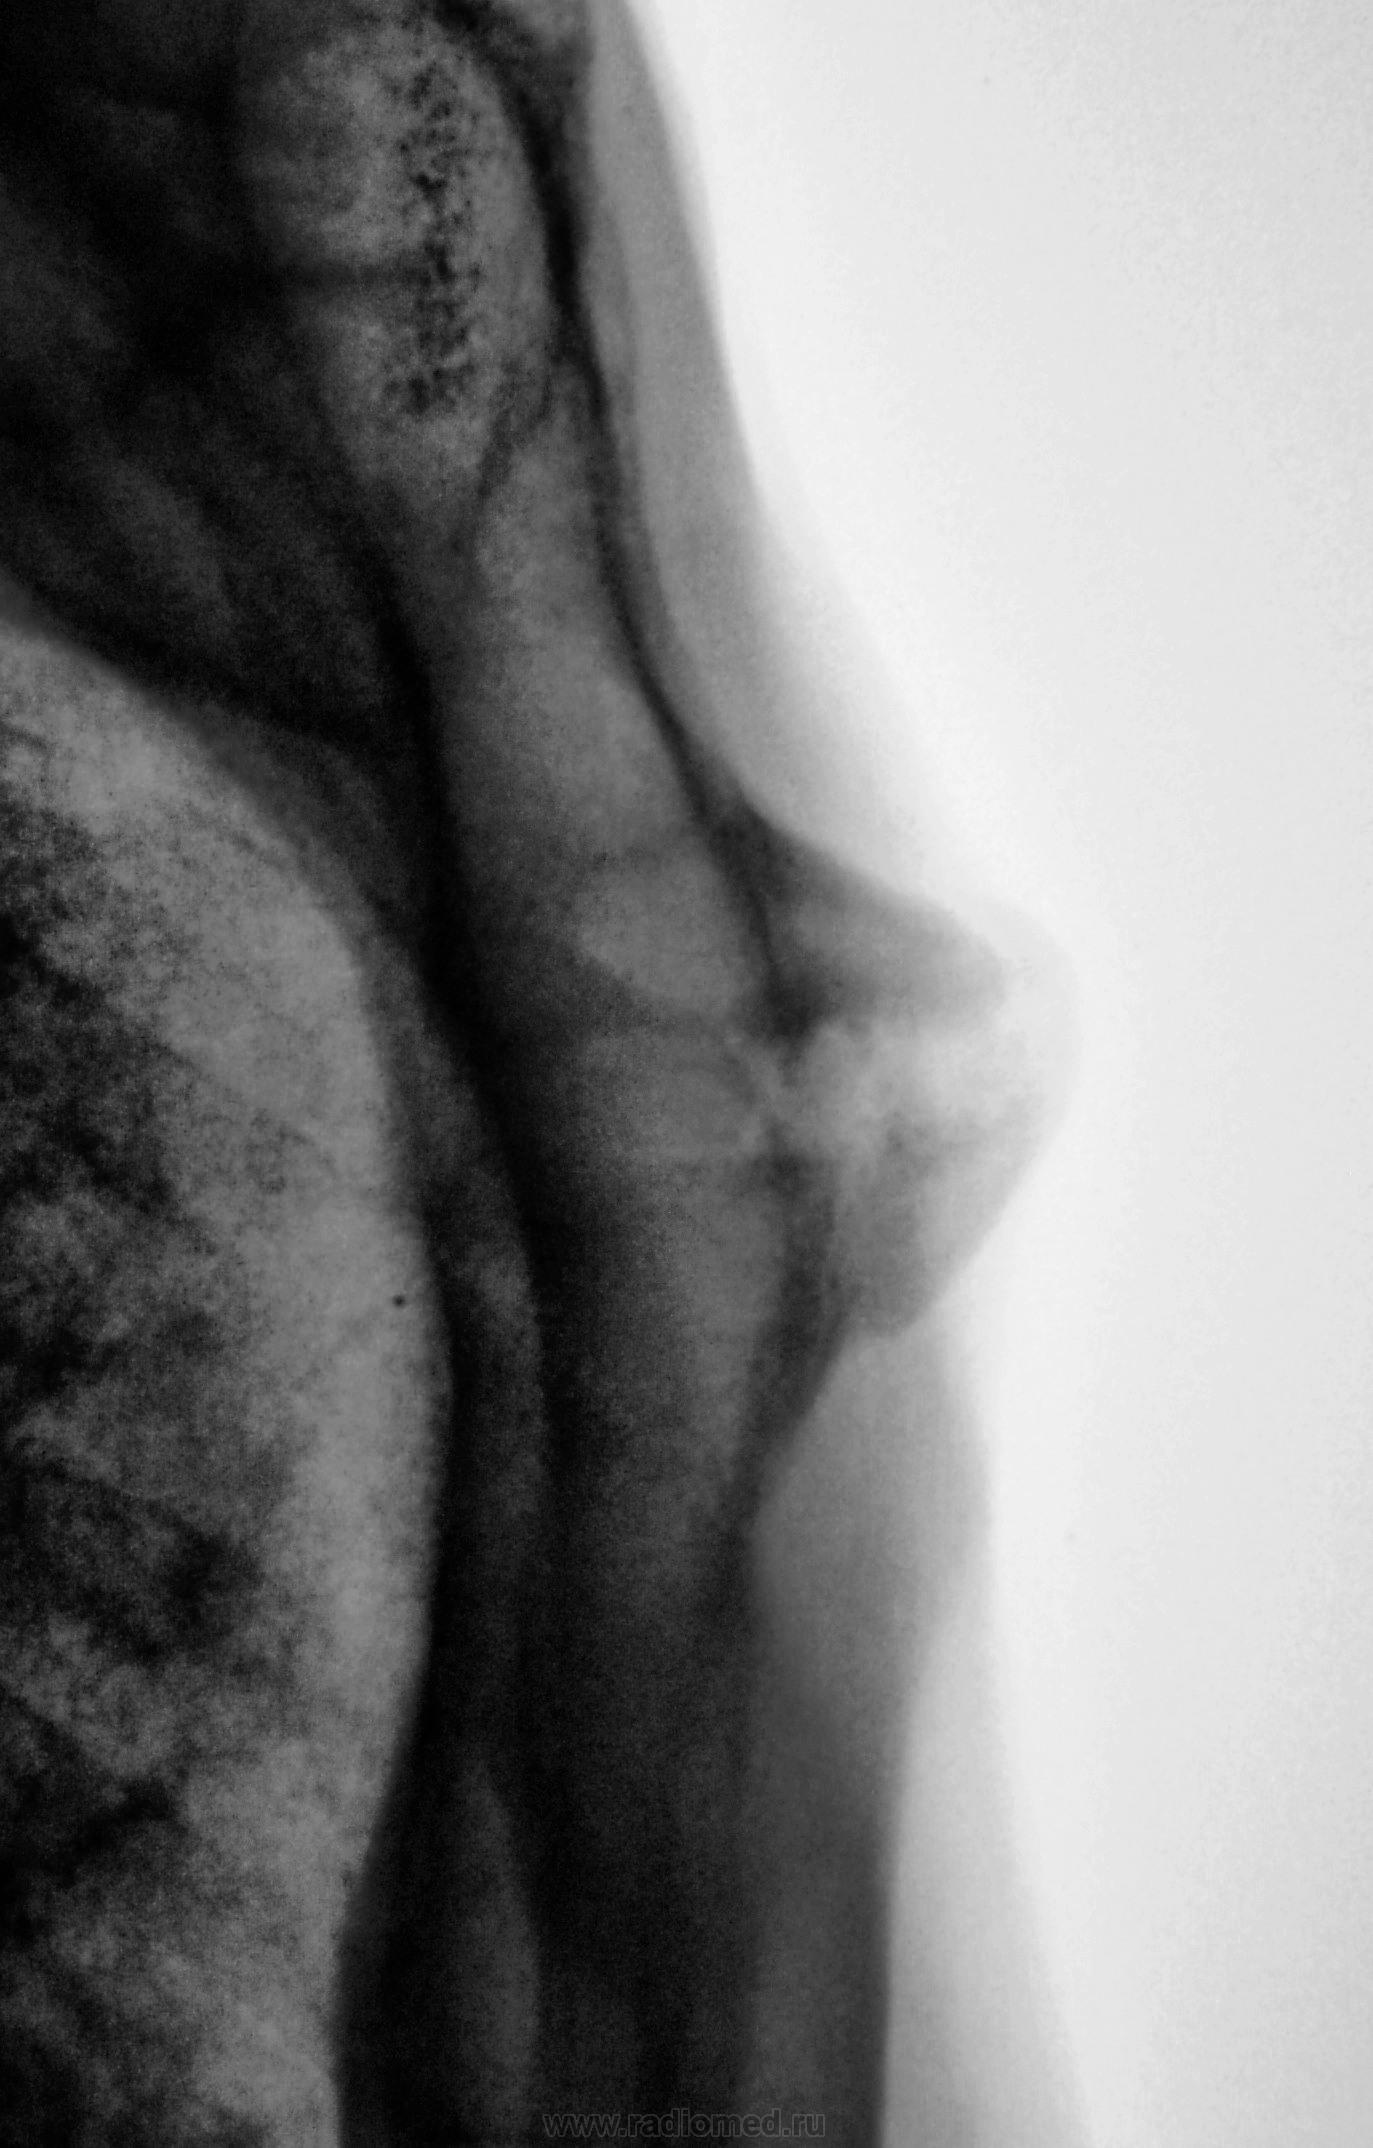

Снимки хорошие, но всё-таки сделал бы томографию. А так, скорее всего, признаки артроза в суставе между телом и рукояткой грудины.

Какой-то остеохондрит типа "Титце".

Артроз то - артрозом, но нет ли тут и асептического некроза нижне-внутреннего края рукоятки грудины....или мне секвестроподобная тень в этом участке "мерещится"?))))

Однако, при таких размеров "шишечке" клиника неблагополучия должна быть!